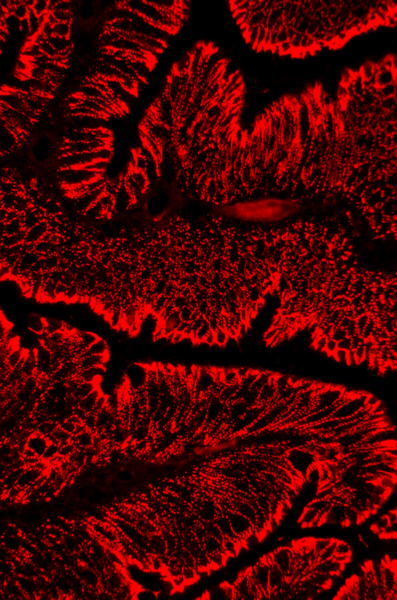

Der für die Gefäßneubildung im Tumor wichtige Rezeptor (VEGFR-2) spielt eine entscheidende Rolle bei der Ausbreitung von Dickdarmkrebs. Ein Impfstoff (Vakzine), der genau auf diesen Rezeptor zielt ist VXM01. Diese oral verfügbare Vakzine wurde von der Firma VAXIMM zur Behandlung von Krebserkrankungen entwickelt. Der Impfstoff zielt darauf eine VEGR-2-spezifische T-Zell-Immunantwort hervorzurufen beziehungsweise diese zu verstärken, die Tumordurchblutung in den behandelten Patienten zu reduzieren und gleichzeitig die Einwanderung von tumorspezifischen T-Zellen zu fördern. In der Phase-1-Studie am Nationalen Centrum für Tumorerkrankungen (NCT) erhalten die Patienten VXM01 als Schluckimpfung. Die Behandlung wird begleitend zu einer Standard-Chemotherapie durchgeführt. Teilnehmen können Patienten mit inoperablem Dickdarmkrebs und Lebermetastasen, bei denen eine oder zwei vorangegangene Chemotherapie-Protokolle und eine Antikörpertherapie versagt haben. Im Verlauf der Studie erfolgen Punktionen der Metastasen, um die Infiltration des Tumors durch Lymphozyten zu untersuchen. Ein umfangreiches immunologisches Begleitprogramm wird innerhalb der Studie durchgeführt.

Die GEKKO Studie ist eine großangelegte wissenschaftliche Studie, die am Nationalen Centrum für Tumorerkrankungen (NCT) in Zusammenarbeit mit gastroenterologischen Praxen im Rhein-Neckar Kreis und den assoziierten Kliniken, wie Chirurgie, Brustzentrum und Thoraxklinik durchgeführt wird. Ziel der Studie ist die Entdeckung und Bewertung neuer Früherkennungstests, mit denen Krebs und seine Vorstufen früher erkannt werden können, denn bei früher Erkennung sind die Heilungschancen der meisten Krebsarten sehr viel besser.

Das Studienprogramm beinhaltet zwei Arme: In Arm A werden in Zusammenarbeit mit gastroenterologischen Praxen in Heidelberg und Umgebung Teilnehmer eingeladen, die zur Durchführung einer diagnostischen- oder Vorsorge-Koloskopie vorstellig werden. In Arm B werden in Zusammenarbeit mit dem Universitätsklinikum Heidelberg Patienten eingeschlossen, die zur Erstbehandlung eines neu diagnostizierten gastrointestinalen Tumors und ausgewählter anderer Krebserkrankungen wie zum Beispiel Lungenkrebs oder Brustkrebs ins Klinikum kommen. Die Teilnahme beinhaltet in beiden Studienarmen das Ausfüllen eines Fragebogens und die Spende von Bioproben (Blut, Urin, Speichel, Stuhl).